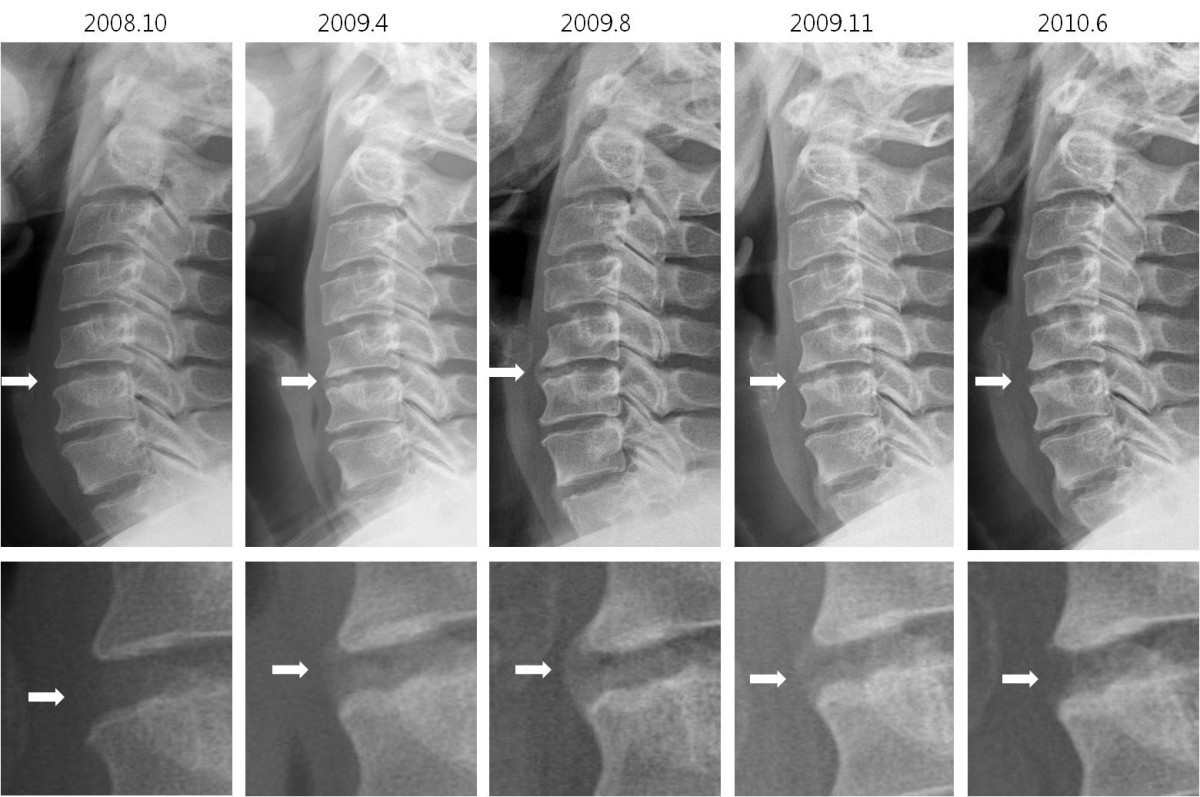

Ankylosing spondylitis (as) inflammation in the spine and/or pelvis causes inflammatory back pain. It has previously been known as spinal osteoarthritis although this is not technically accurate. Here, we present a case of bilateral pleural effusion in 38 years. Ankylosing spondylitis (as) is a chronic inflammatory rheumatic disease that mainly affects the spine. Conventional plain radiography of the spine and pelvis is the current standard for imaging in as, as it can visualise chronic changes such as syndesmophytes.

This is a very different process than spondylosis because spondylosis is degenerative while spondylitis is inflammatory. Conventional plain radiography of the spine and pelvis is the current standard for imaging in as, as it can visualise chronic changes such as syndesmophytes. Ankylosing spondylitis (as) is a chronic seronegative spondyloarthritis associated with the major histocompatibility antigen hla b27. Acute anterior uveitis (aau) is common in ankylosing spondylitis (as). Spondylitis is a chronic disease that may persist throughout life.